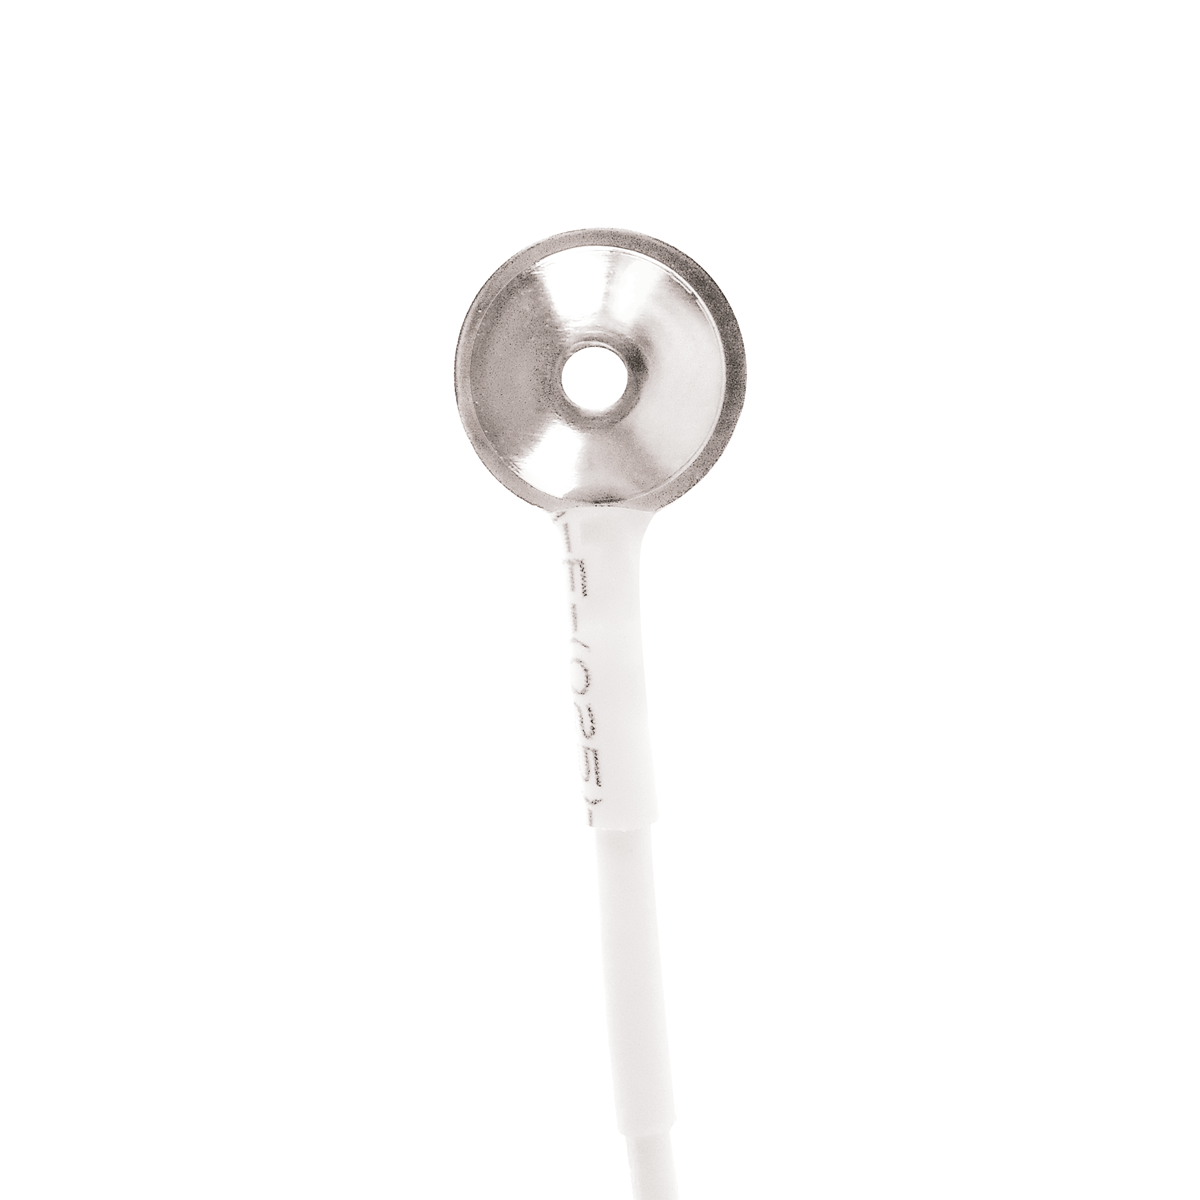

Os Eletrodos Concha de Prata são a escolha profissional para exames de EEG e PSG, combinando alta qualidade técnica e segurança. Fabricados com conector Touch Proof (pino de segurança), concha banhada a ouro e fios de Kevlar ultra-resistentes, garantem durabilidade excepcional e precisão na captação de sinais elétricos cerebrais.

– Concha banhada a prata para condutividade superior e redução de interferências.

– Banho de Ouro: Garante sinal limpo e estável, essencial para diagnósticos precisos.